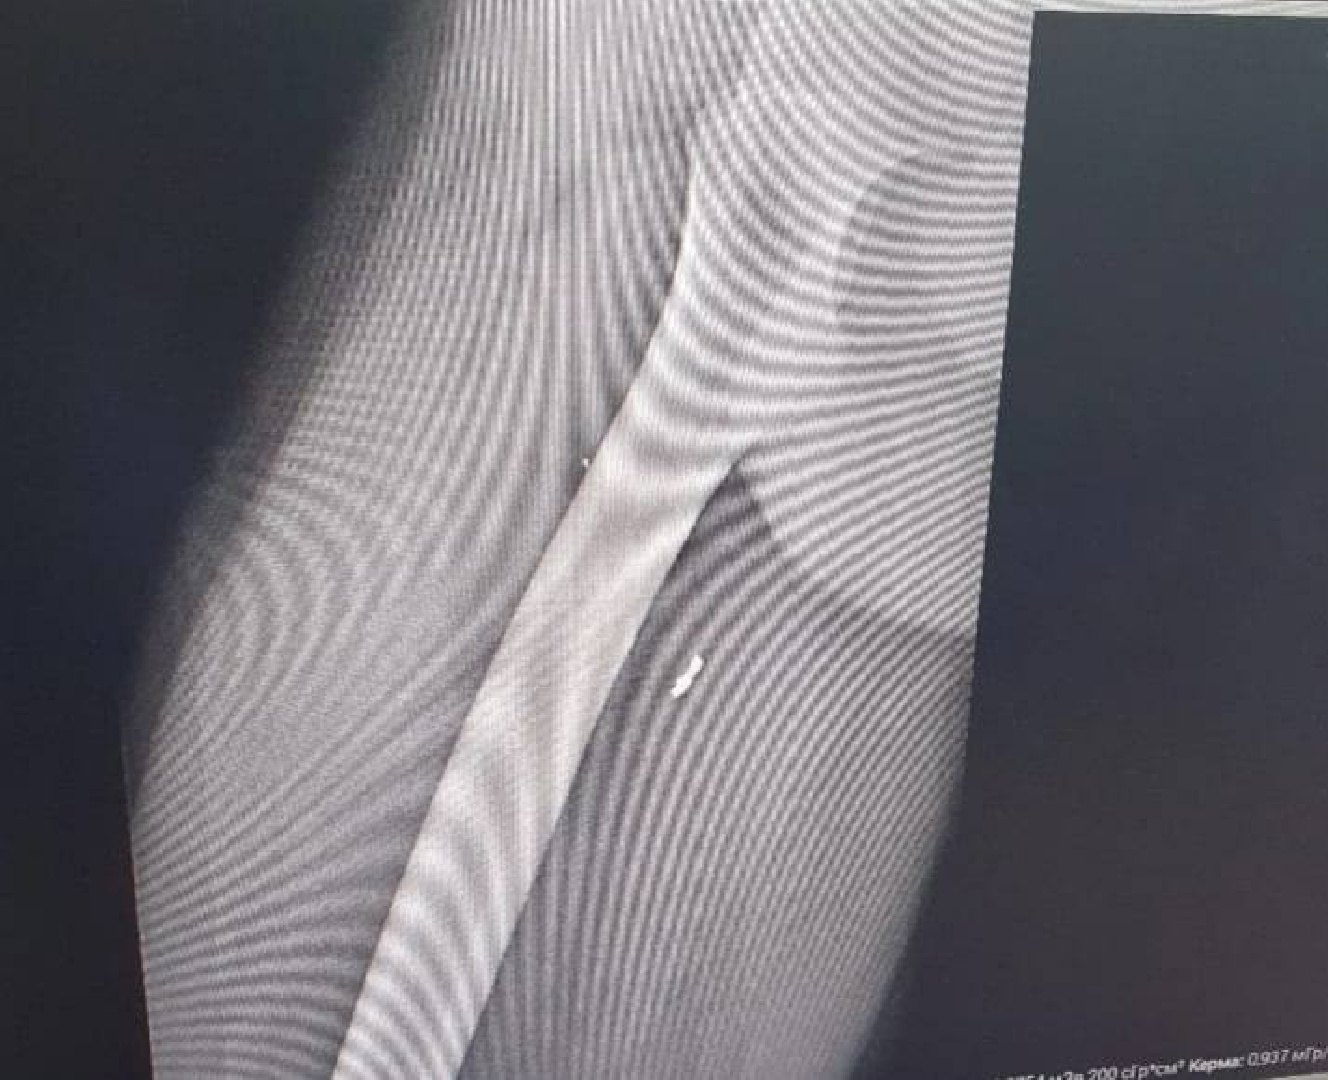

Воскресенские врачи удалили осколок снаряда из бедра 24-летнего парня, вернувшегося с СВО В областную больницу городского округа Воскресенск обратился 24-летний молодой человек с паховой грыжей, после осмотра парень сообщил, что приехал домой в отпуск со спецоперации и сообщил врачам о наличии в бедре осколка миномётного снаряда. После необходимых исследований врачи нашли глубоко в бедре парня осколок длиной 1 сантиметр

«Сначала мы провели операцию по удалению паховой грыжи. А через 2 дня под рентген-контролем с помощью аппарата С-дуга провели малоинвазивную операцию по удалению осколка снаряда – извлекли его через разрез диаметром всего в 1 сантиметр», – сообщил хирург Воскресенской областной больницы, заслуженный работник здравоохранения Московской области Владислав Бурдаков.